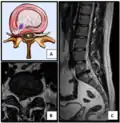

Herniated lumbar disc

Lumbar disc herniations occur in the back, most often between the fourth and fifth lumbar vertebral bodies or between the fifth and the sacrum. Here, symptoms can be felt in the lower back, buttocks, thigh, anal/genital region (via the perineal nerve), and may radiate into the foot and/or toe. The sciatic nerve is the most commonly affected nerve, causing symptoms of sciatica. The femoral nerve can also be affected and cause the patient to experience a numb, tingling feeling throughout one or both legs and even feet or a burning feeling in the hips and legs.[22] A herniation in the lumbar region often compresses the nerve root exiting at the level below the disc. Thus, a herniation of the L4–5 disc compresses the L5 nerve root, only if the herniation is posterolateral.

Herniated disc at C6–C7 level

Cervical disc herniations occur in the neck, most often between the fifth and sixth (C5–6) and the sixth and seventh (C6–7) cervical vertebral bodies. There is an increased susceptibility amongst older (60+) patients to herniations higher in the neck, especially at C3–4.[23] Symptoms of cervical herniations may be felt in the back of the skull, the neck, shoulder girdle, scapula, arm, and hand.[24] The nerves of the cervical plexus and brachial plexus can be affected.[25]

• Magnetic resonance imaging is the gold standard study for confirming a suspected LDH. With a diagnostic accuracy of 97%, it is the most sensitive study to visualize a herniated disc due to its significant ability in soft tissue visualization. MRI also has higher inter-observer reliability than other imaging modalities. It suggests disc herniation when it shows an increased T2-weighted signal at the posterior 10% of the disc. Degenerative disc diseases have shown a correlation with Modic type 1 changes. When evaluating for postoperative lumbar radiculopathies, the recommendation is that the MRI is performed with contrast unless otherwise contraindicated. MRI is more effective than CT in distinguishing inflammatory, malignant, or inflammatory etiologies of LDH. It is indicated relatively early in the course of evaluation (<8 weeks) when the patient presents with relative indications like significant pain, neurological motor deficits, and cauda equina syndrome. Diffusion tensor imaging is a type of MRI sequence used for detecting microstructural changes in the nerve root. It may be beneficial in understanding the changes that occur after herniated lumbar disc compresses a nerve root, and might help in differentiating the patients that need surgical intervention. In patients with a high suspicion of radiculopathy due to lumbar disc herniation, yet the MRI is equivocal or negative, nerve conduction studies are indicated.[44] T2-weighted images allow for clear visualization of protruded disc material in the spinal canal.